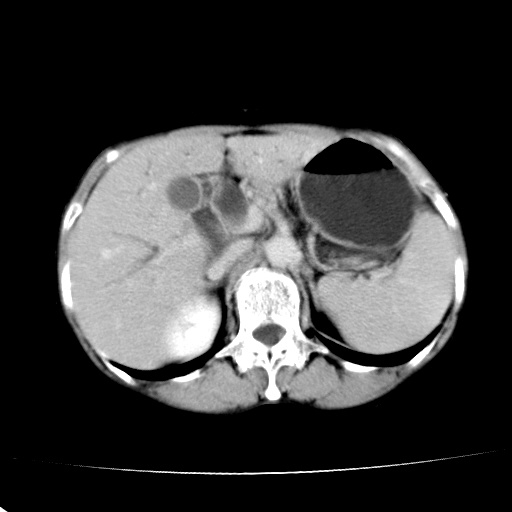

以下是引用jiangjing在2008-6-3 13:36:00的发言:[br]支持 胰头癌------肝内外胆管扩张,胰管扩张,胰头增大,增强见结节状轻度强化影,双管征明显

以下是引用卜一在2008-6-3 14:40:00的发言:[br]支持:胰头癌!(肝内外胆管扩张,胆囊高度扩张,胰管扩张,胰头增大,增强见结节状强化,明显低于胰腺强化密度,并明显见双管征)

以下是引用dyqct在2008-6-3 14:54:00的发言:[br]支持 胰头癌伴肝内外胆管扩张,胰管扩张,胰头增大,增强见结节状轻度强化影,双管征明显。肠系膜上静脉已受侵(已不能手术),建议离子植入治疗吧。